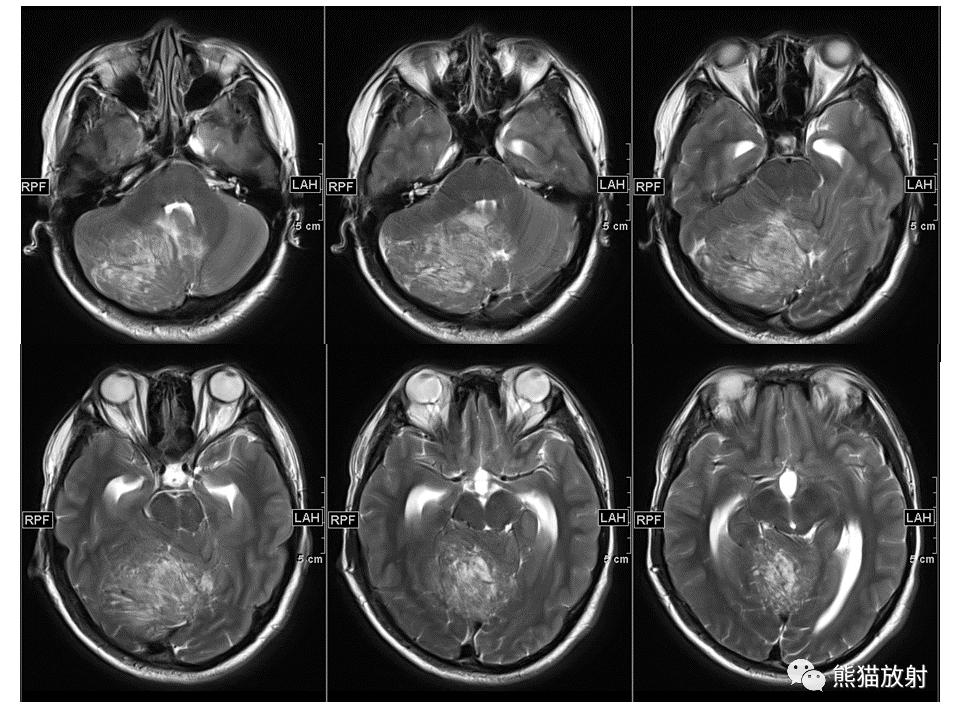

【PPT】小脑发育不良性神经节细胞瘤 VS 成人型髓母细胞瘤-1